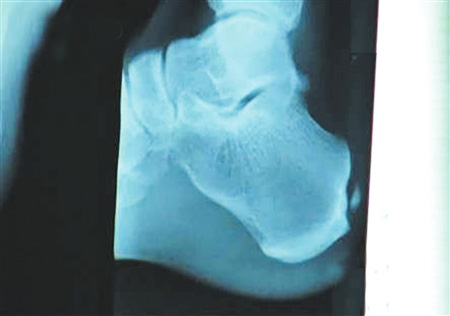

手術要取出的鈣化物就在這里。 圖片來源:華西都市報

北京時間12月6日凌晨,備受關注的中國飛人劉翔在休斯頓赫曼紀念醫院的跟腱手術成功結束。